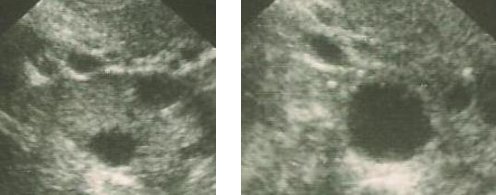

Tratamento simples e mais barato, consiste no uso de doses baixas de medicações hormonais (comprimidos ou injeções) que provocam o crescimento de um folículo único ou de poucos folículos. Deve-se realizar um acompanhamento ultra-sonográfico seriado, pelo qual se mede o tamanho dos folículos dominantes para se orientar os melhores momentos para o casal manter relações sexuais.